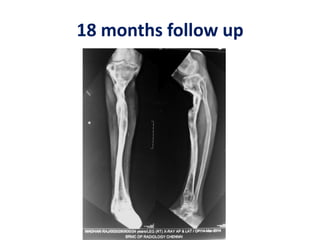

18 months follow up

25 years male Trafficaccident 2.5 years back Lost other limb above knee Allograft failed 20 cm gap Stem cells in a large gap non union

After allograft removal 20 cm gap  Tibialisation of fibula  Segmental transfer

Good regeneration BMAC Stemcell infiltration